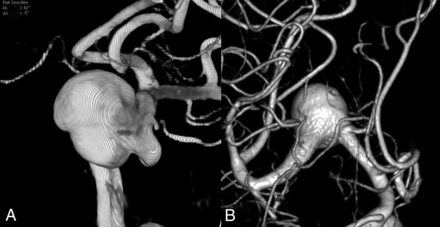

The parameters evaluated were aneurysm shape (saccular or fusiform), size, and neck diameter; intra-aneurysmal thrombus and incorporated vessel status; stenosis and curvature of the parent artery in the region of the aneurysm neck; balloon angioplasty status; and contrast medium stagnation during angiography as potential predictors of the effects of FD.9,12 The curvature of the parent artery involving the aneurysm neck region was classified as outer or non-outer, depending on the location of the aneurysm neck (Fig 1). Because the pore density of flow-diverter stents is greatly affected by curvature, metal coverage is relatively higher over the inner curve than over the outer curve.13 If the aneurysm neck lies on the outer curve, any effects of flow-diverter stents are likely to be reduced. The stagnation grade of contrast medium was categorized as arterial, capillary, or venous on pre- and post-FD cerebral angiography. Immediately after flow-diverter stent (FDs) deployment, it was determined whether the stagnation grade increased. In addition, prolonged stagnation (for >1 minute) was recorded after FDs deployment. We assume that balloon angioplasty changes the stent pore density because the flow-diverter stents are braided and the aneurysm neck lies in the unconstrained zone.

This image shows the curvature type of the parent artery involving the neck region of the aneurysm. A, Non-outer type. B, Outer type.